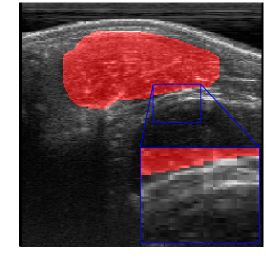

Rib Eye Area (REA). This image dataset consists of ultrasound images of the Longissimus dorsi muscle between the 11th and 13th ribs of cattle. The goal is to automatically calculate the rib eye area (REA), an important region for decision making during cattle breeding. The main challenge is the uncertainty in the REA annotation, since the image is noisy and even experts have difficulty in delimiting the borders of this region. Fig. 3 presents examples of images and the annotation made by a specialist. We can observe that some borders are absent and depend on the subjectivity and knowledge of the annotator. To evaluate the segmentation methods, 76 images with resolution were obtained and labeled by an expert. Due to the number of images, the division of the images in training and testing followed 5-fold cross-validation.

REA dataset. This image dataset has high uncertainty during labeling due to noise from the ultrasound image. In some cases, the border of REA is not completely visible and must be estimated by the specialist. Therefore, the proposed approach becomes essential to obtain accurate segmentation at the edges. The segmentation examples in Fig. 6 show that the baseline was not able to define the REA correctly due to the uncertainty of the labeling. On the other hand, the proposed approach presents results close to the specialist in regions that the border needs to be estimated.